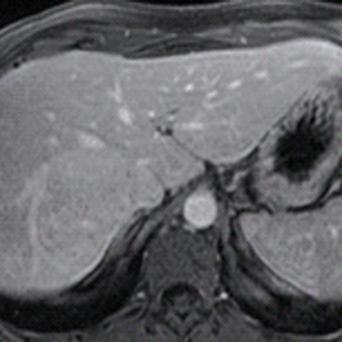

Microangiopathie thrombotique

La microangiopathie thrombotique (MAT) est une urgence médicale. Elle recouvre plusieurs pathologies aux mécanismes, tableaux cliniques et traitements distincts. Les progrès récents dans la compréhension de leur physiopathologie ont permis de mieux les identifier et les classifier, tandis que des thérapeutiques spécifiques en ont grandement amélioré le pronostic. Une identification précoce est donc cruciale.